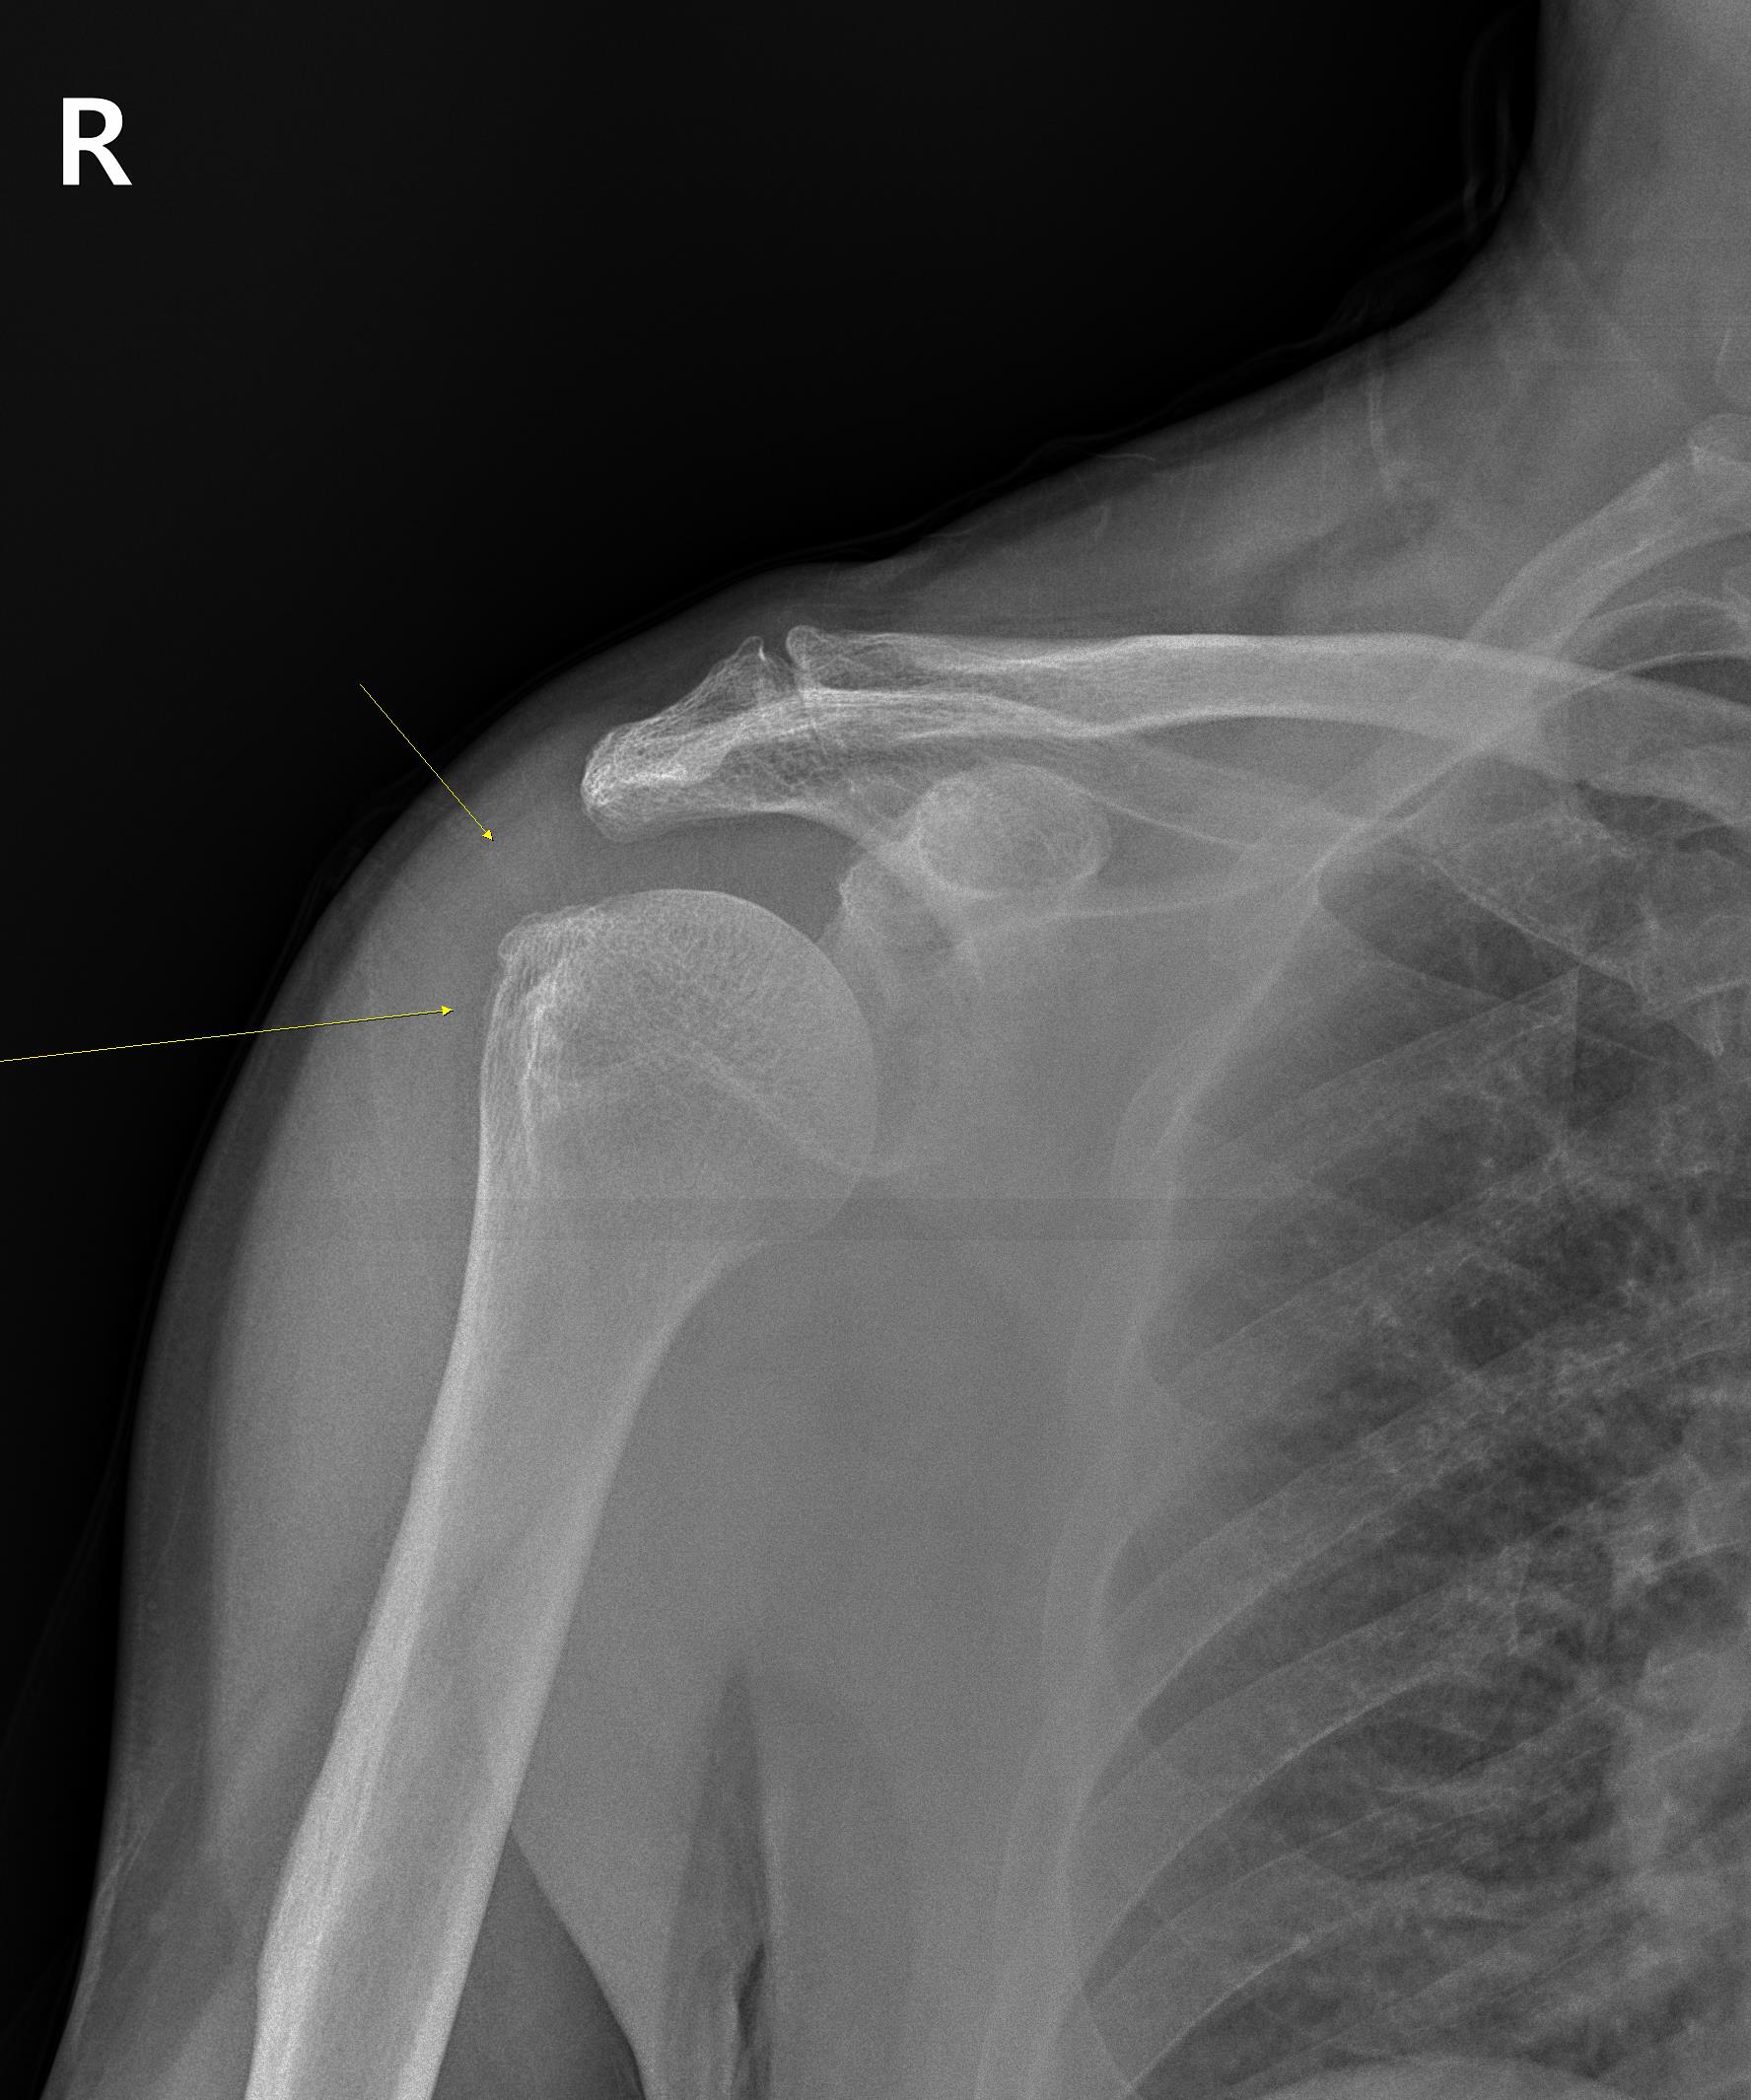

웨이트 트레이닝을 하면서 어깨가 아파졌다는 환자, 우선 x-ray를 찍었습니다. 사진을 보니 우측 상완골 대결절 부위에 골극이 보입니다. 골극(bone spur)은 쉬운말로 '뼈가 자라있다'라고 말하곤 하는데요... 뼈의 특정 부위에 오랫동안 염증이 반복되는 등의 자극이 반복되면 관찰되는 소견입니다.

골극이 보이는 상완골 대결절 부위는 극상근 힘줄의 부착부위입니다. x-ray상에 이상 소견이 보인다는건 극상근 힘줄에도 문제가 있을 가능성이 높다는 이야기죠. 힘줄 상태를 확인하기 위해 초음파 검사를 진행했습니다. 결과는...